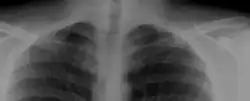

Die obere Schlüsselbeingrube ist durch einen in der Tiefe tastbaren, knochenharten Tumor verstrichen. Der Nachweis gelingt mit speziell eingestellten Röntgenaufnahmen sowie mit weiterführenden bildgebenden Verfahren, wie CT oder MRT. Oft ist die Halsrippe ein Zufallsbefund ohne jeden Krankheitswert.